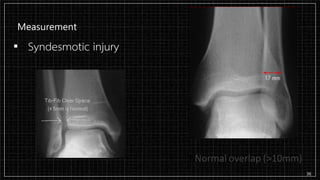

Measurement

▪ Syndesmotic injury